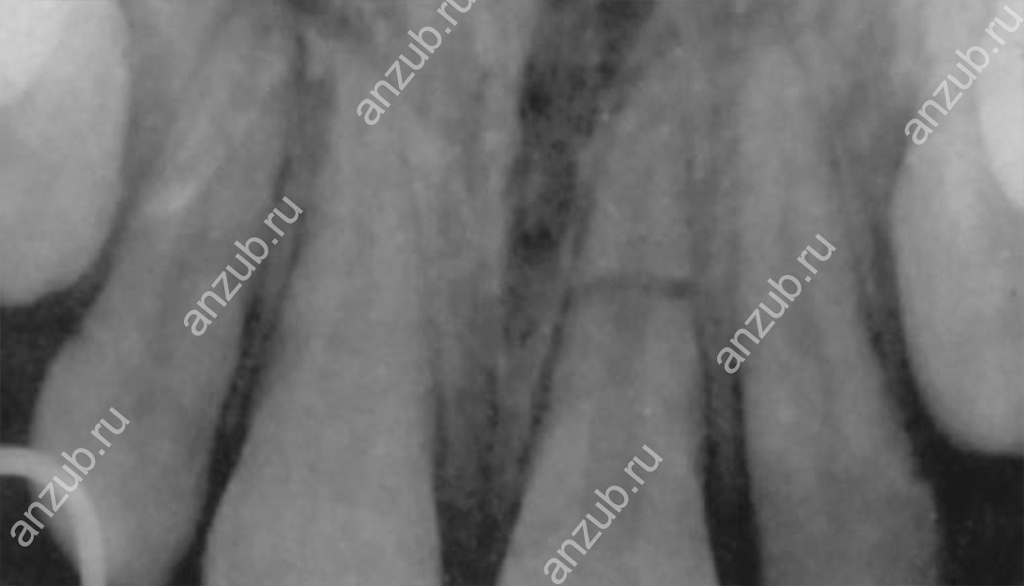

Наиболее информативным методом диагностики будет рентген или, лучше всего, компьютерная томография. С их помощью можно оценить не только место перелома и линию разлома, но и состояние окружающих тканей.

В каждом случае лечение будет подбираться индивидуально. Сегодня даже при малейшей возможности сохранить зуб в хорошей стоматологии врачи ею воспользуются. Методы применяются различные в зависимости от клинической картины. Возможна резекция удаление пульпы и пломбирование каналов, укрепление штифтом, обеспечение неподвижности.

Если же травмы сильные, разломы большие и пролегают вдоль, по диагонали, имеются осколки, то спасти зуб уже, как правило, нельзя. Тогда проводят его удаление и последующее восстановление. Важно только своевременно обратиться к врачу, чтобы исключить осложнения!